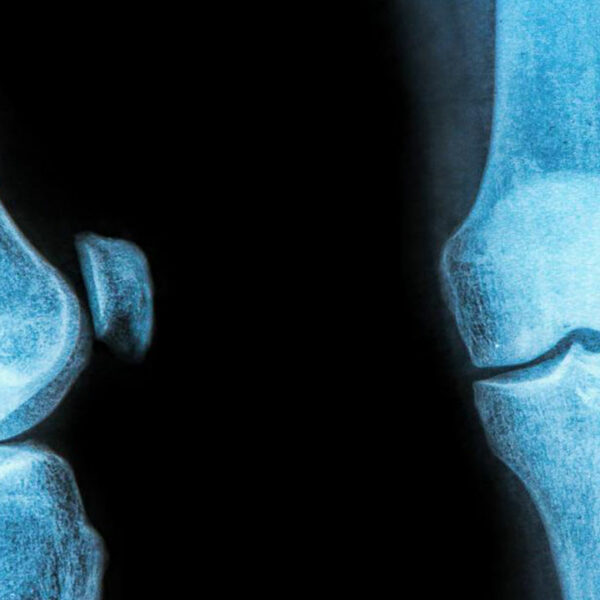

The rubbery C-shaped disc cushioning your knee is a meniscus. There are two menisci in each knee. One at the inner side and the other on the outer side. It is this meniscus that helps to keep your knee steady. It balances your body weight around your knee. If there is a tear in the meniscus, you will experience a lot of pain. It will also prevent the proper functioning of your knee.

You can distinguish the types of meniscus tear based on its symptoms. The types can range from being minor to more severe tear. A minor tear involves a slight swelling of the knee and can last up to 2 to 3 weeks. If the swelling has aggravated after a sudden twist or turn, you might be experiencing a partial tear. In this regard, a moderate medial or lateral meniscus tear brace can ease the pain.

In the case of a moderate tear, the pain lies in the center of the knee. The swelling is visible over 1 or 2 days. In this case, walking is possible, but the bending of the knee might cause stiffness. The symptoms arrive and withdraw over a prolonged period. They can cause enough trouble unless treated at the right time. A meniscus tear brace with two sturdy aluminum uprights and bilateral hinges will be beneficial in the case of a moderate tear.

A severe tear is considered as an extreme case. A severe tear tends to happen when the meniscus flows into the knee joint area. You will find it difficult to walk, bend, or turn your knee. You might feel that your knee seems locked up. Sometimes, the swelling returns after 2 to 3 days of the injury. So, often you might not even realize that you suffer from a meniscus tear. A thigh and calf strap will help to compress the knee joint, effectively relieving the pain.